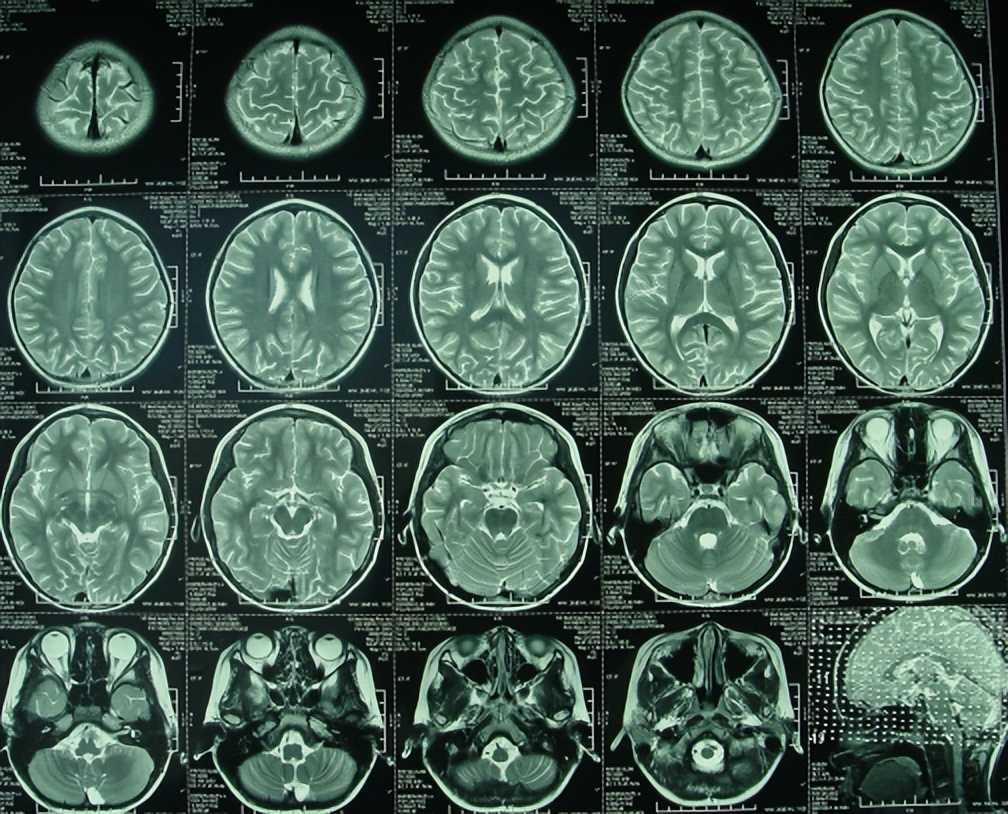

在2010年5月23日(发病后17天)转入小儿神经内科后,腰穿脑脊液检查的结果提示白细胞数显著增多,达到>2000的严重程度,进一步查头颅核磁(图-1)后,诊断为“化脓性脑膜炎”,抗感染治疗(万古霉素,美罗培南等)治疗18天。

图-1:2010年5月23日头颅核磁